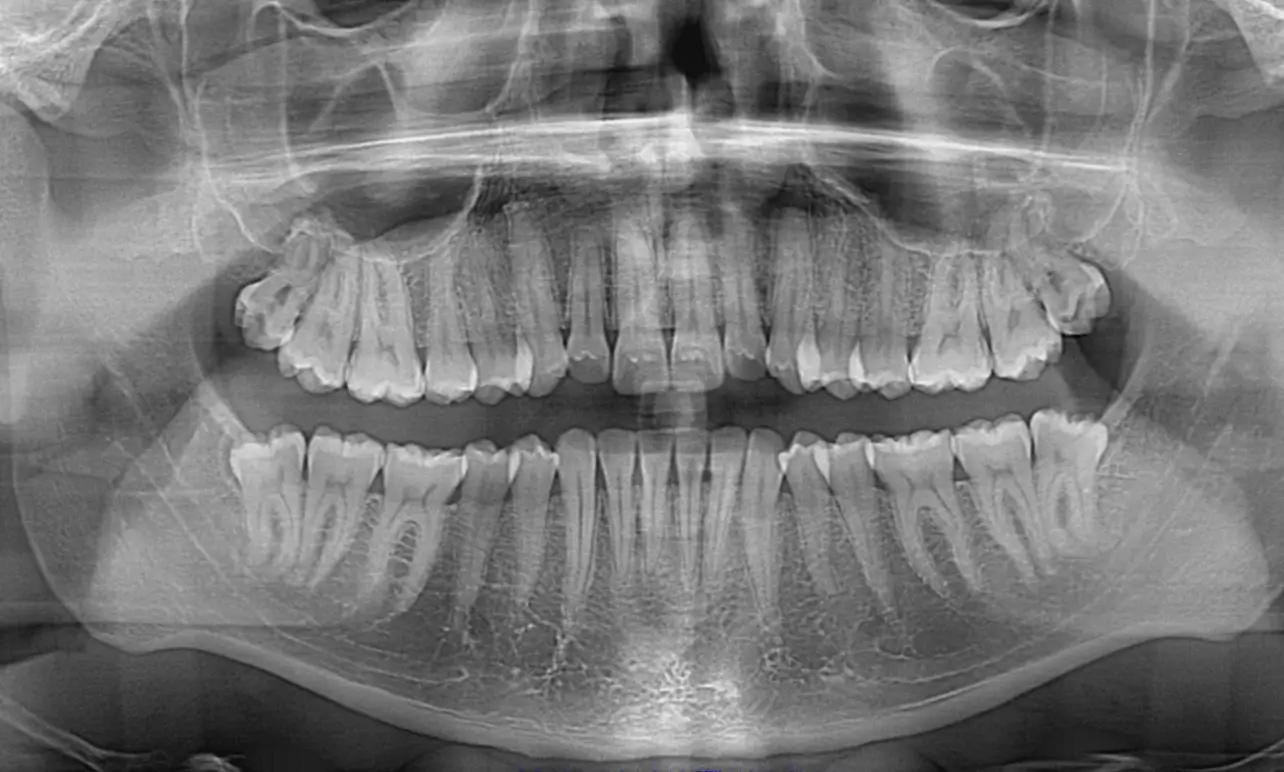

Exodoncias de dientes incluidos

Consiste en la remoción quirúrgicas de dientes mal posicionados como las cordales, dientes retenidos y/o supernumerarios, este procedimiento se puede hacer con sedación endovenosa en casos complejos